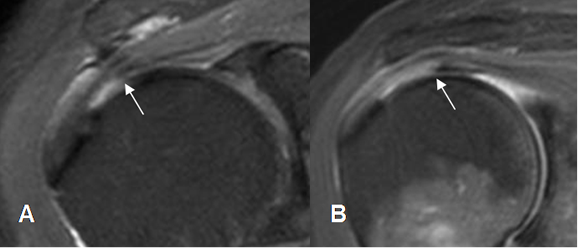

Fig 116. Ruptura parcial del supraespinoso.

A: RM coronal en T2 y B: RM coronal en STIR. Ruptura parcial del tendón supraespinoso hacia la superficie humeral (Flechas delgadas), con fibras íntegras en la superficie bursal. (Flechas gruesas).

Fig 117. Ruptura parcial del supraespinoso.

A: RM coronal en T2 y B: RM coronal en STIR. Ruptura parcial del tendón supraespinoso hacia la superficie bursal (Flechas delgadas), con fibras íntegras en la superficie humeral. (Flechas gruesas).